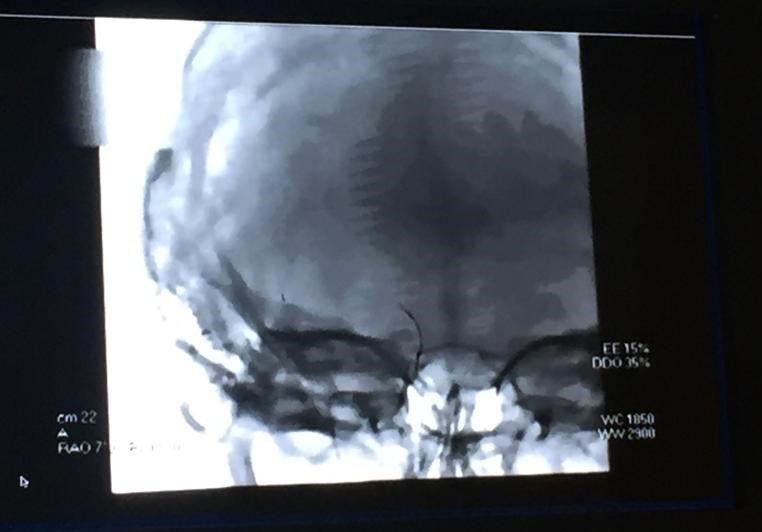

Cases